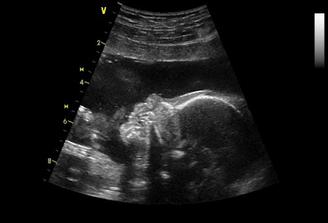

Po prvním neúspěchu se nám to hned povedlo. V 5.-6.týdnu jsem si poležela v nemocnici kvůli špinění a do konce 12.týdne beru hormony. Další kontrola až 3.12.. Na UTZ byl i budoucí taťka a viděli jsem, jak mimi dělá kotrmelce. Zdá se, že nos bude mít po manželovi-velký. Brali mi krev na testy a 19.12. jdu na první screening. Další kontrola u MUDr. bude 23.12. Screening dopadl na 1 s hvězdičkou, šance na poškození miminka jsou minimální (huráá) srdíčko bije a od hlavičky k prdelce už máme 7 cm. Termín porodu nám na screeningu posunuli o dva dny tj. na 27. června.